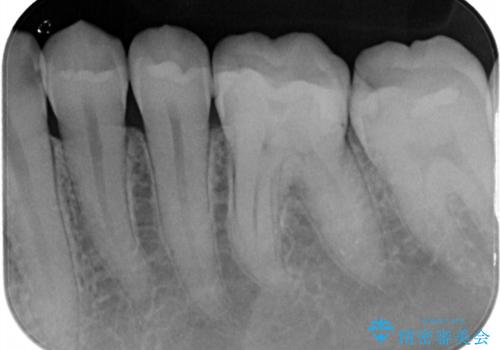

1番奥の歯のセラミック治療をご希望されましたが、レントゲンなどの診査の結果、大きな虫歯などもありませんでした。

それよりも奥から2番目の歯のほうが、適合不良の銀のつめものが入っており、大きな虫歯が疑われました。

虫歯の大きさや形を加味して、1番奥を保険治療、奥から2番目をセラミック治療で行うことになりました。